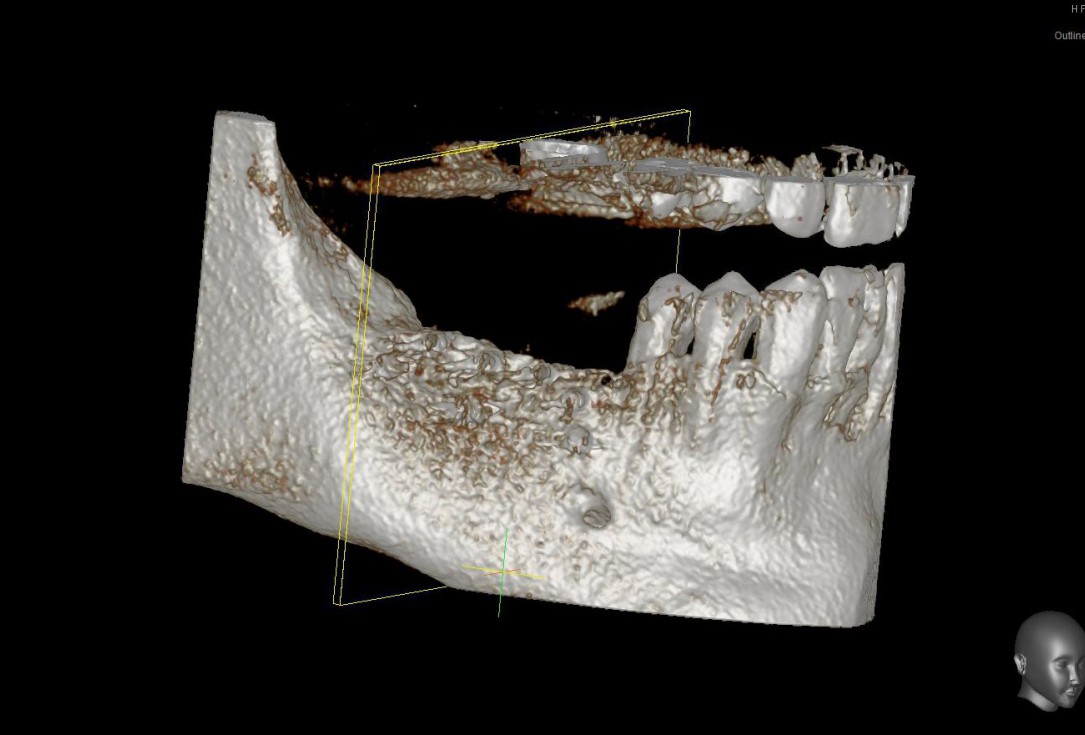

01/28 - Model of the initial defect computed from a CBCT scan - buccal viewThree-dimensional augmentation with maxgraft® cortico - Dr. R. Würdinger

Model of the initial defect computed from a CBCT scan - buccal view